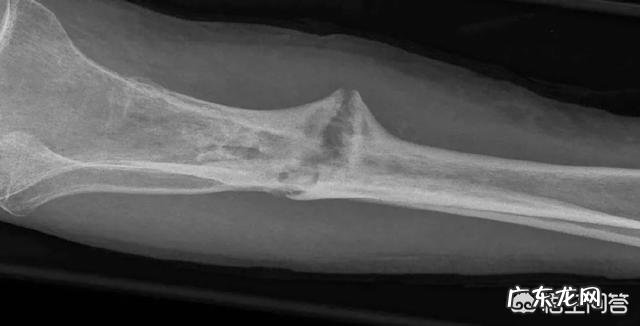

人的身高是由骨骼的长度决定的,而骨骼的长度又是由骺板的软骨细胞不断繁殖生长决定的,一般情况下人到了17岁至20岁骺板就停止生长发育 。这就是你的身高停留在现在这个高度的原因 。

断骨增高毕竟是要借助外力,把本来健康的腿打断,然后再用外力进行拉伸,以达到增高的目的,其中需要适应这种外力的不仅有骨头,还有神经、血管、肌肉组织等 。危险性是非常高的,而且那种痛苦是常人难以忍受的 。

那么如何进行延长呢,简单的说就是锯断一个人的腿,然后人为的拉长一段距离,再安装一个固定的肢体延长器,那么通过人体组织的自我修复能力,新生的骨骼会填补那段,人为拉长的距离,所以大长腿就这么出现了 。

不过这个手术虽然是真的,但代价可不是一般的大,这个手术一旦失败了,至少会产生一下几种严重后果,其中第一种就是下肢坏死,由于骨骼在生长的过程中,如果伤害到了神经或者血管,人可能会下肢瘫痪,甚至是直接截掉整条腿,所以这个代价你们懂得 。

另外还有一种后果,就是长短腿,由于骨骼在生长的过程中,固定骨骼的延长器出现问题的话,人极有可能出现一个腿长,一个腿短的后果,而且真要是出现了这种情况,你需要重新在锯断一次腿,重新让骨骼长回来 。

所以断骨增高术看起来很美,但危险非常大,这个手术本来就不是让人长高,而是运用在小儿麻痹症后遗症,以及天生骨骼缺陷患者身上的 。